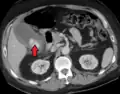

Right upper quadrant abdominal ultrasound is most commonly used to diagnose cholecystitis.[1][26][27] Ultrasound findings suggestive of acute cholecystitis include gallstones, pericholecystic fluid (fluid surrounding the gallbladder), gallbladder wall thickening (wall thickness over 3 mm),[28] dilation of the bile duct, and sonographic Murphy's sign.[13] Given its higher sensitivity, hepatic iminodiacetic acid (HIDA) scan can be used if ultrasound is not diagnostic.[13][14] CT scan may also be used if complications such as perforation or gangrene are suspected.[14]

Acute cholecystitis as seen on ultrasound. The closed arrow points to gallbladder wall thickening. Open arrow points to stones in the GB -

Acute cholecystitis with gallbladder wall thickening, a large gallstone, and a large gallbladder -